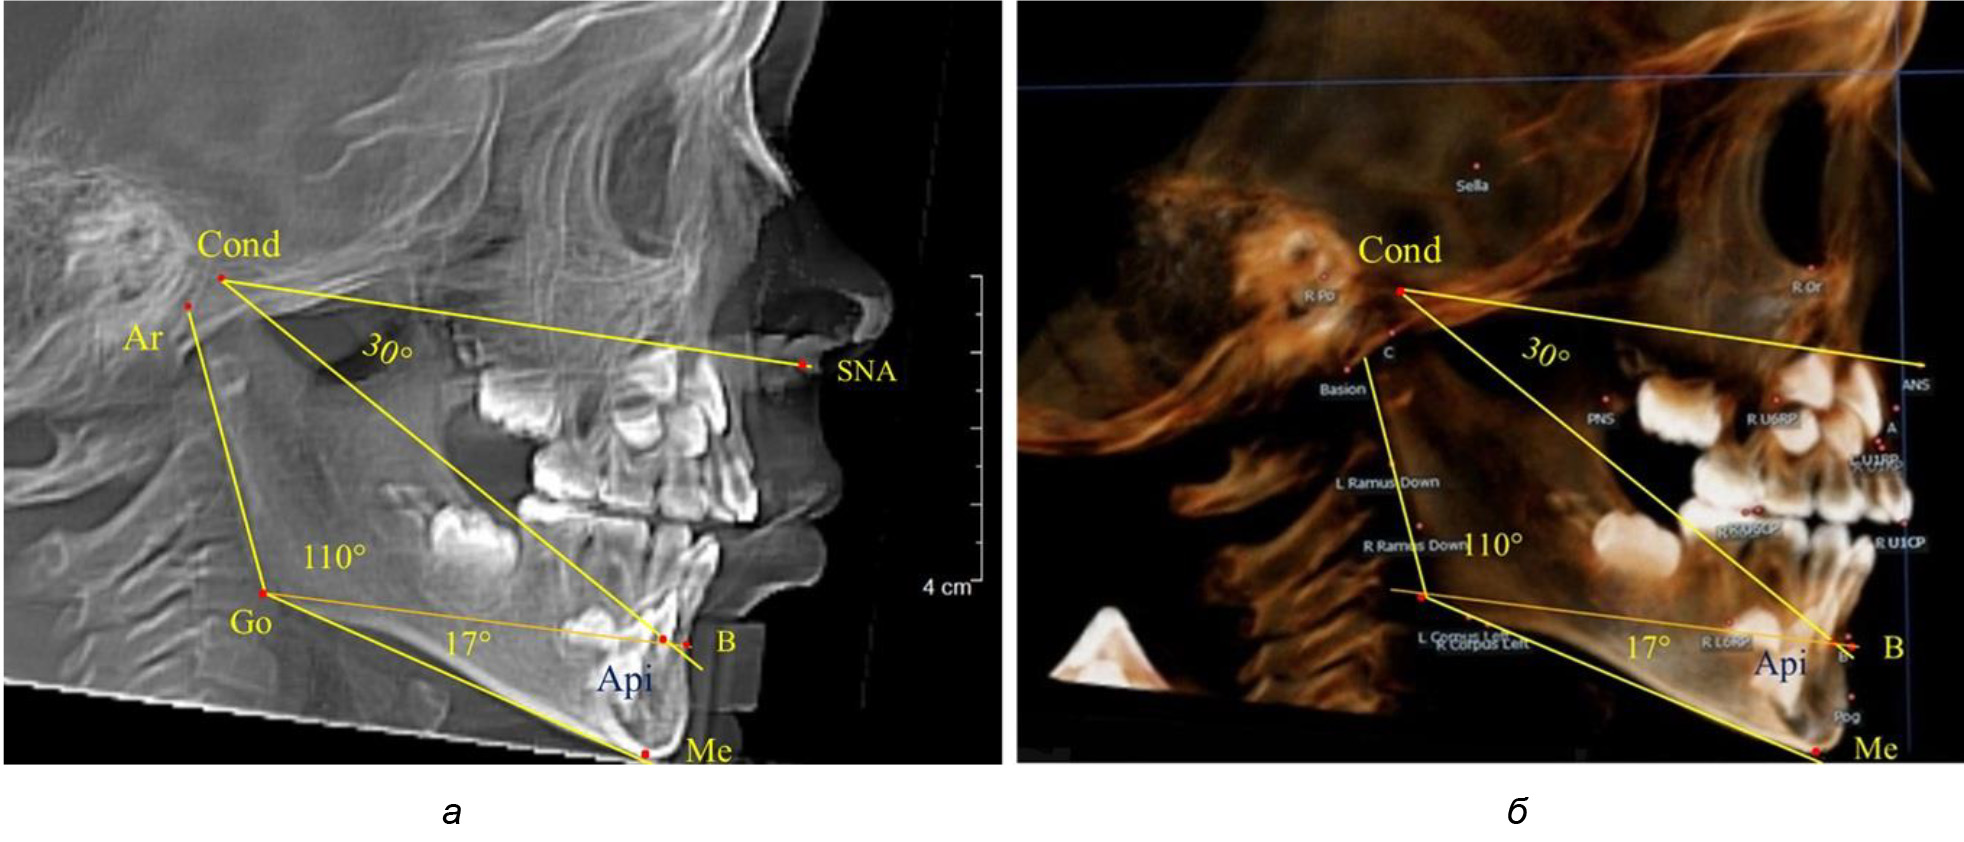

Таким образом, в периоде молочного прикуса с оптимальными окклюзионными соотношениями, несмотря на линейные размеры в вертикальном и сагиттальном направлении, которые, безусловно, меньше параметров взрослых людей, величина основного угла гнатической части лица SNA-Cond-Api соответствовала параметрам людей с полностью сформированным физиологическим прикусом постоянных зубов. Анализируя данные рентгенограмм детей в периоде сменного прикуса, отмечено, что величина основного угла гнатической части лица SNA-Cond-Api, так же как в молочном и постоянном прикусе, в норме составляла от 28 до 32°. В то же время угол нижней челюсти и его составляющие отличались вариабельностью параметров при различных показателях нижнечелюстного угла. Достоверных различий угла гнатической части после смены нижних медиальных резцов и прорезывания первых постоянных моляров (4 ребенка) не было; происходил очередной этап подъема высоты прикуса и увеличение линейных размеров костей гнатической части, однако угловые параметры были относительно стабильны. После смены всех резцов и замены первых молочных моляров первыми премолярами (6 человек) увеличивались линейные размеры при сохранившихся угловых показателях гнатической части лица (рис. 5).

Рис. 5. Варианты ТРГ после прорезывания ППМ и нижних резцов (а), всех резцов и первых премоляров (б)

Таким образом, в период сменного прикуса с оптимальными окклюзионными соотношениями, несмотря на увеличение линейных размеров в вертикальном и сагиттальном направлении, по сравнению с прикусом молочных зубов, величина основного угла гнатической части лица SNA-Cond-Api соответствовала показателям как постоянного, так и молочного прикуса с физиологическими окклюзионными соотношениями.

После смены всех молочных зубов (анализ 9 ТРГ) и после прорезывания вторых постоянных моляров (7 человек) происходил очередной этап подъема высоты прикуса с увеличением размеров костей гнатической части лица. Однако величина основного угла гнатической части лица SNA-Cond-Api, так же как в молочном и сменном прикусе, в норме составляла (30,02 ± 1,25)°, что не имело достоверных различий (р ˃ 0,05) с аналогичным параметром, анализируемом в других группах исследования. Угол нижней челюсти и его составляющие отличались вариабельностью параметров при различных показателях нижнечелюстного угла (рис. 6).

Рис. 6. Варианты 3D рентгенограмм детей после смены всех молочных зубов (а) и после прорезывания вторых моляров (б)